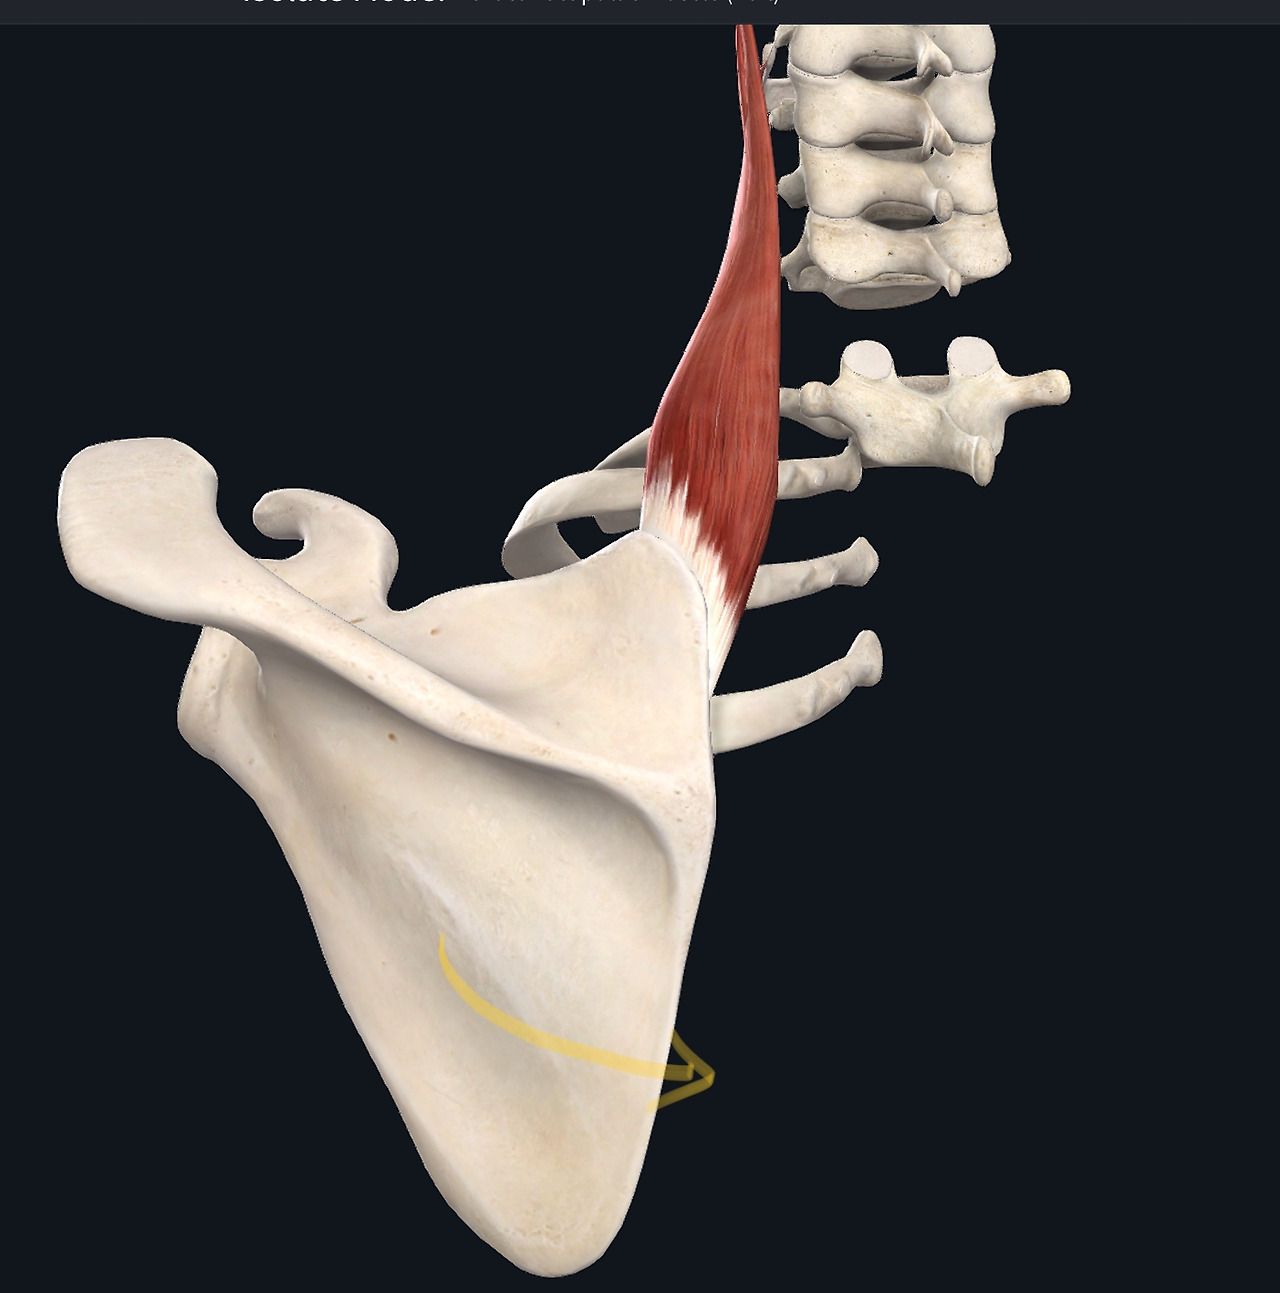

2. 앞톱니근(전거근)

왼쪽이 돌림근띠(1,2,3,어깨밑근은 어깨뼈에 가려짐), 우측이 앞톱니근

어깨치료에 있어 빠질 수 없는 중요한 근육은 어깨돌림근띠(회선근개)이다. 어깨돌림근띠는 어깨뼈에서 위팔뼈 머리 쪽에 부착된 4개의 근육을 총칭한 것인데, 어깨돌림근띠는 위팔뼈 머리가 어깨뼈의 관절면에 제자리 잡도록 도와주는 역할을 하는 근육이다. 실험에 따르면 손에 25파운드(약 11.3kg) 무거운 가방을 들었을 때 어깨돌림근띠의 작용만으로도 이 동작을 수행할 수 있었다고 하니 이 근육의 평상시 작용 능력이 놀라울 따름이다. 어깨 주변의 큰 근육들은(어깨세모근, 위팔두갈래근, 위팔세갈래근)은 근전도(EMG, electromyo graphy) 상 변화가 나타나지 않았다고 한다.4,5 어깨돌림근띠의 강화는 팔을 쉬거나 움직일 때 관절면의 제 위치에 위치하도록 도와줄 것이다. 앞톱니근은 어깨뼈를 위쪽 돌림(화살표 방향)시켜주는 역할을 한다. 어깨뼈의 위쪽 돌림은 팔을 끝까지 드는데 필수적으로 동작이다. 봉우리빗장 관절의 손상은 팔의 움직임 끝에서 주로 통증을 야기시키므로 어깨뼈 위쪽 돌림에 도움을 제공하는 앞톱니근의 강화는 팔 동작의 개선과 통증 감소에 효과적 방법이다. 간략한 운동 방법은 다음과 같다.